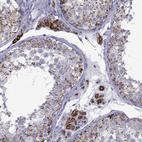

Immunohistochemistry analysis in human adrenal gland and lymph node tissues using HPA044393 antibody. Corresponding FDXR RNA-seq data are presented for the same tissues.